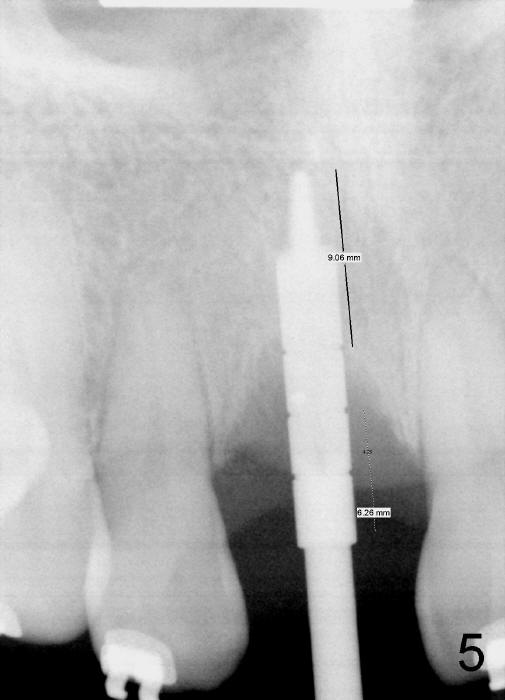

Osteotomy is being enlarged with a 3 mm reamer (Fig.5). Although there is bone height deficiency, the bone density is quite high. Autogenous bone is being harvested while the reamers (2.5 and 3 mm) are being used. Osteotomy depth is more (9.06 mm) than the pilot drill (7.61 mm in Fig.4).